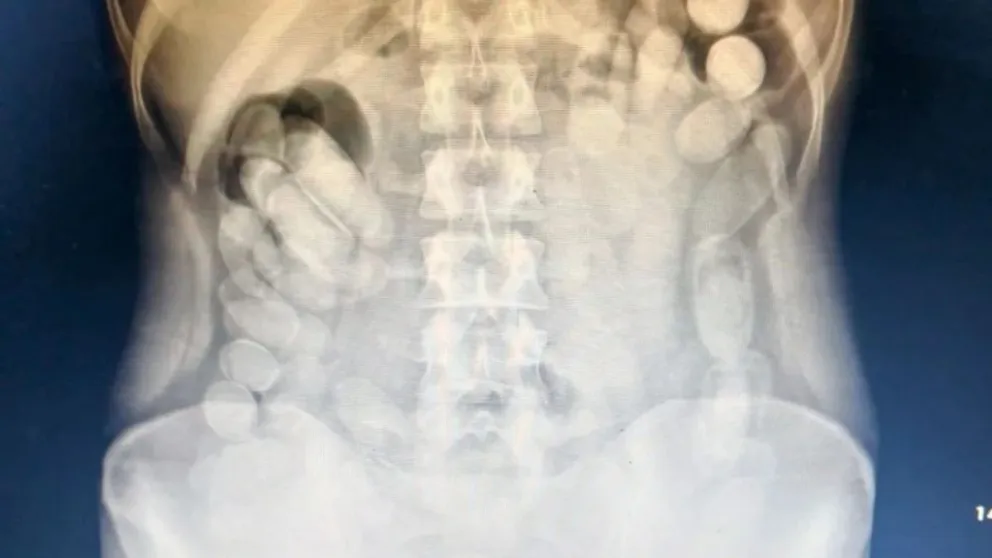

Archivo de noticias Noticias del 2025-06-18 Millonaria estafa virtual a un empresario de Roca Denuncian 200 despidos en la arenera petrolera NRG Figueroa y Weretilneck lanzan mensaje a Milei desde el Primer Encuentro por la Norpatagonia Fue condenado a 8 años de prisión por abusar sexualmente de su hija en Cipolletti Causa Vialidad: todos los condenados ya se presentaron en Comodoro Py Nueva Jornada de Salud Visual este domingo en Ingeniero Huergo Muerte de Valentín: la causa sigue a juicio y dictaron prohibición de acercamiento entre el anestesista y la mamá de la victima Un nene cayó desde el puente ferroviario: está fuera de peligro Río Negro pagará salarios y aguinaldo en los primeros días de julio Bomberos de Regina festeja su 65° aniversario y lo celebrará el sábado con un acto Docentes del IUPA brindaron una capacitación folclórica en Regina Alumnos de Huergo y Mainqué realizarán la Promesa de Lealtad a la Bandera La Escuela Secundaria para Jóvenes N°1 lanza concurso docente en el marco de su nuevo plan de estudios El petróleo se dispara tras el conflicto en Medio Oriente: ¿sube la nafta? Horror: apuñaló 20 veces a su pareja y convivió con el cuerpo varios días Regina será sede de un torneo provincial de fútbol inclusivo: conocé a “Los Pelusas” Diputados piden expulsar a Espert por sus insultos a Florencia Kirchner La aplicación para que los docentes rionegrinos den el presente, tiene carácter de declaración jurada Proyecto VMOS: Trabajo acompañó las evaluaciones técnicas de oficios Cerró la primera quincena de junio en Bariloche con un aumento del 6% de movimiento turístico respecto 2024 Teleférico Cerro Otto inauguró el Mirador del Lago Mundial de Clubes 2025: qué partidos se juegan hoy miércoles 18 de junio Una pasajera de un colectivo llevaba 100 cápsulas de cocaína en el estómago Video: manejaba borracho, atropelló a una mujer y la arrastró 50 metros El Gobierno ordenó evacuar la embajada argentina en Irán Un vecino de Regina rompió dos cubiertas por el mal estado de la ruta: por qué la justicia condenó a la aseguradora El peronismo marcha a Plaza de Mayo para apoyar a Cristina Kirchner Cómo funciona la tobillera electrónica que deberá usar Cristina Kirchner El clima: pese al sol, continúa el frío en la región Bahco celebró con éxito la tercera edición de su concurso de poda en frutales en Huergo VIDEOS: vandalizaron el domicilio de José Luis Espert ¿Qué son los misiles hipersónicos que Irán lanzó sobre Israel? Ir al Día anterior Seleccionar fecha: Ir